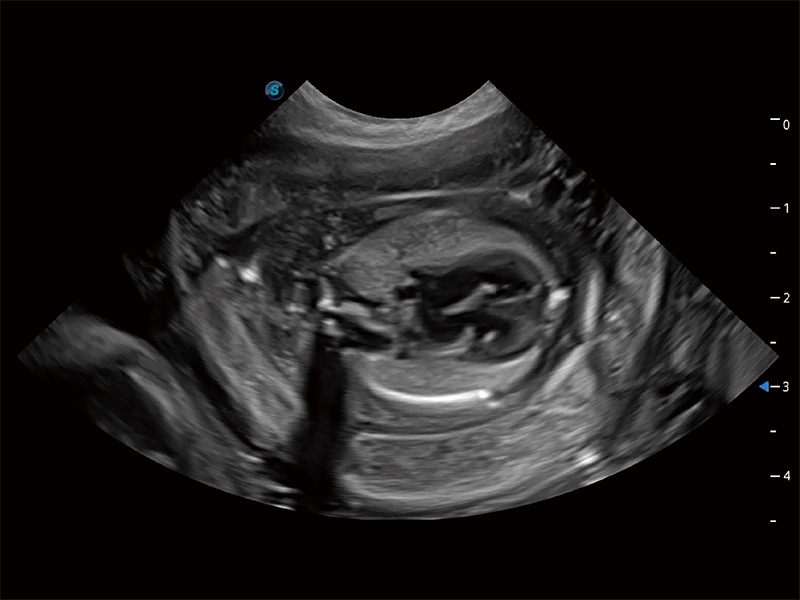

動物是人類最親密的朋友和最值得信賴的伙伴。開立醫(yī)療也一直致力于探索動物專用的超聲影像解決方案。全新推出的ProPet系列,是開立在動物超聲影像智能化、專業(yè)化、精準化的一次跨越式革新。動物不能用言語來表述自己的不適,通過超聲影像,ProPet系列搭建了動物醫(yī)生與不同物種溝通的“橋梁”,為動物醫(yī)生注入了“治愈之力”。 ProPet 80 是開立醫(yī)療匠心打造的一款高端動物專用彩超,采用性能卓越的全新硬件架構(gòu),極大提升超聲系統(tǒng)的運行效率和數(shù)據(jù)處理能力,幫助動物醫(yī)生從容應對日益增多的挑戰(zhàn)性病例和日益多樣化的臨床需求。

高性能和先進的臨床應用工具可以為動物醫(yī)生提供臨床信心。ProPet 80 搭載了先進的腹部和淺表應用工具,幫助醫(yī)生在日常臨床實踐中發(fā)揮前所未有的作用。

ProPet 80 全新的動物超聲智能軟件和豐富的探頭群,為動物醫(yī)生提供了高清晰度和精細分辨率的圖像,無論在寵物、馬科、畜牧還是實驗室動物等應用中都可以輕松應對,為您的日常工作帶來滿意的體驗。